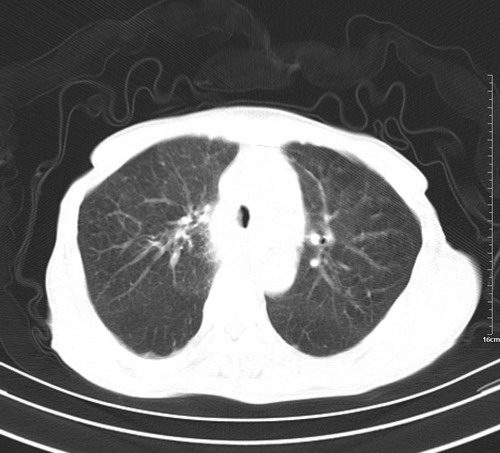

病人,女,79岁,主要因腹疼二月入院,彩超,肝,胆,脾,未见异常,胸透上消化道造影未见异常,化验白细胞增高,内科医生让做胸部ct检查,因为熟人多做了腹部(外科会诊考虑胆囊炎).现ct片如下请假各位战友.

1 气管旁、隆突下淋巴结明显肿大,肝左叶外侧段低密影,都考虑转移。

肺癌,纵隔淋巴结转移,肝左叶病变考虑为转移病灶。

后中纵隔团块影,伴气管、食道受压移位,首先考虑转移瘤,肝s5段低密度灶。建议增强检查,另外其结肠是否有问题请提供,右肺部分肺叶局限含气增多,考虑局限肺气肿。